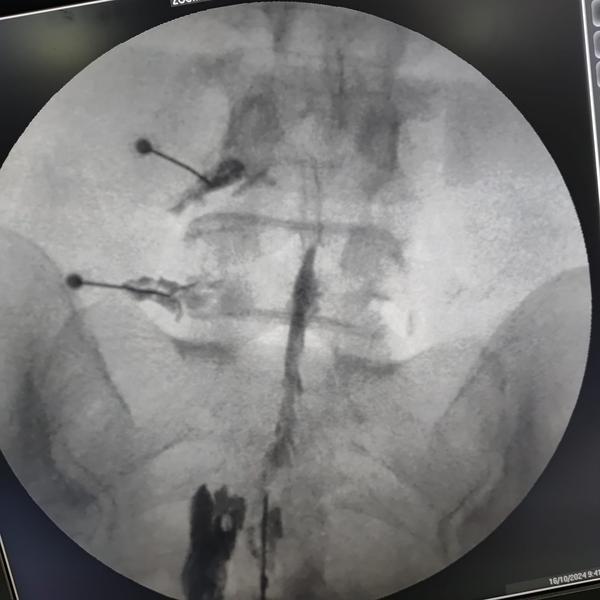

Transforaminal L4,L5,S1 nerve root block !

Transforaminal nerve root block + Caudal epiduroplasty !